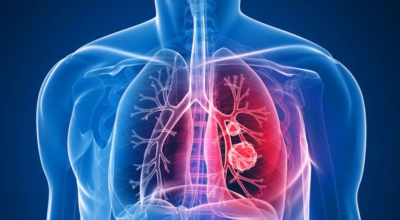

폐암의 초기증상 중에는 흉통이 있습니다. 위치에 따라 요통으로도 진행이 되기도 하는데요 흉통이 생기는 경우는 폐의 가장자리에 폐암이 발생할 때 나타나게 됩니다. 흉막에 암이 인접해 위치하게 되면 바늘로 콕콕 찌르는 듯한 흉통을 느끼게 되며 폐암이 갈비뼈나 다른 부위로도 전이될 경우에도 흉통이 발생하고 요통으로도 발전 할 수 있답니다.

상대정맥증후군 이란 상대정맥 주위에 폐암이 생겨서 상대정맥을 압박할 때 발생되는 증상을 말해요. 혈액순환 장애가 생겨서 머리와 팔이 심하게 붓게 되고, 호흡곤란, 가슴 정맥 돌출 과 같은 증상이 일어날 수 있어요.